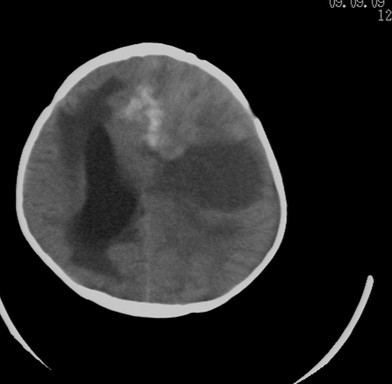

考虑脑占位并出血,脑疝形成。

考虑左侧颞顶叶占位并出血,脑疝形成

考虑左侧颞顶叶占位并出血,脑疝形成!

考虑左侧颞顶叶占位并出血,脑疝形成!梗阻性脑积水

考虑左侧颞顶叶占位并出血,脑疝形成,梗阻性脑积水。

1)考虑左侧额颞顶叶肿瘤并卒中;建议行进一步检查。2)大脑镰下疝,左侧颞叶沟回疝。3)脑积水(梗阻性)。

考虑左侧额颞顶占位并出血,脑疝形成。支持

考虑左侧额颞顶叶占位并出血,脑疝形成,梗阻性脑积水。